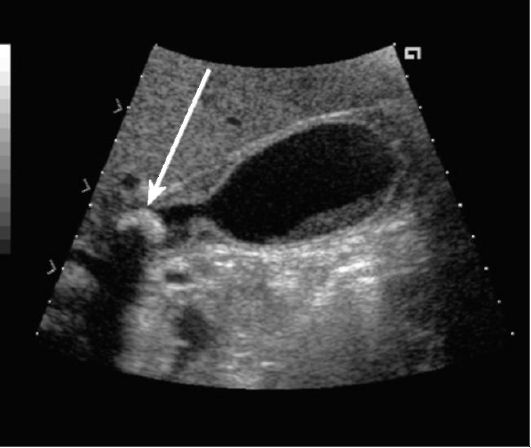

В свежем узи есть большие буквы,как их понять и что изменилось с желчным?

Наташ , ну судя по всему ДИП - диффузные изменения печени, других вариантов не нашла и дальше в циферах, а вот с желчным , как не пыталась.. чет мне это слово ничего не напоминает. кроме как приграничн, но как его там применить

ДНПВ--диаметр нижней полой вены..Жёлчный--"бумеранг"..То есть есть перегиб и по форме похож на него.Раньше был овоид, т.е. в форме яйца..Перегиб в с/3--средней трети..Yugo69 писал(а):рысь

Узи делала одна и та же врач на одном аппарате.

Впринципе все осталось практически без изменения.я так думаю

Такая деформация желчного может давать внепеченочную симптоматику болей в правом подреберье,тошноты и т.д.